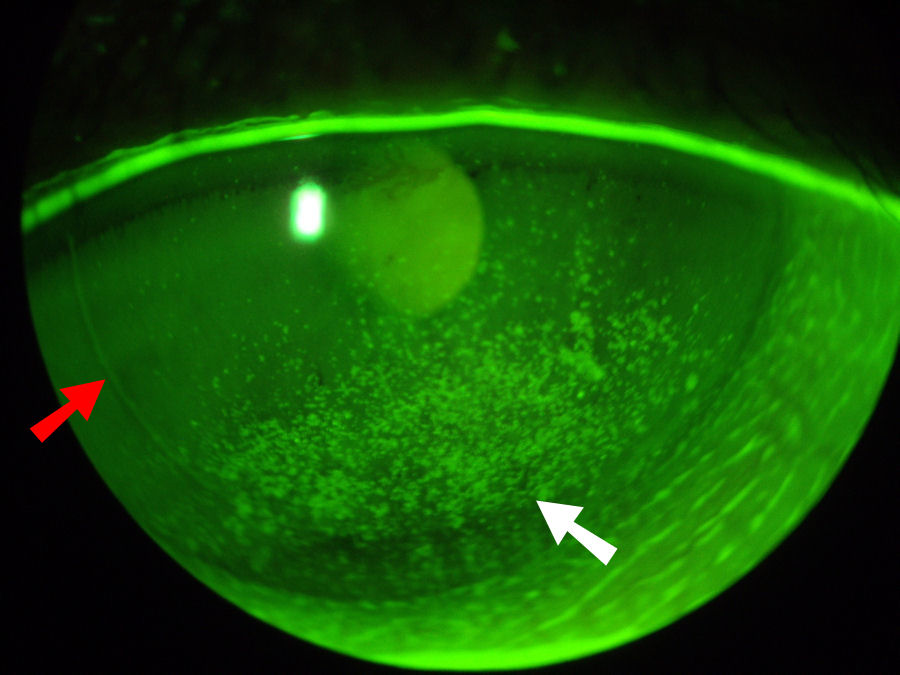

На фотографии ниже показаны серьезные сухие глаза у пациента, перенесшего операцию LASIK с последующим ФРК . Красная стрелка указывает на край лоскута LASIK. В глаз был закапан зеленый краситель, который выделяет участки поражения поверхности и потерю поверхностных клеток (эпителия). Белая стрелка на этой фотографии указывает на большой сухой область роговицы, которая выглядит как скопление пятен. Нажмите на фотографию, чтобы увеличить.